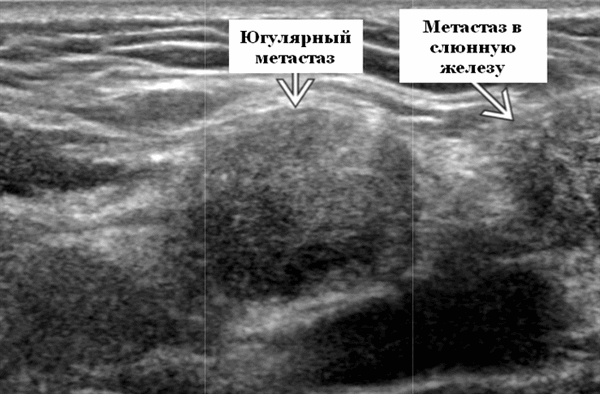

- ± Метастатические шейные лимфатические узлы

Визуализация. Общие особенности. Само по себе ультразвуковое сканирование метастазов в околоушные лимфоузлы неспецифична. Одиночные или множественные околоушные образования. Хорошо выраженный или плохо выраженный лимфоузел (экстранодальное распространение), однородный или неоднородный с внутренним некрозом. На УЗИ с ЦДК внутриузловая васкуляризация или усиление кровотока. Патология связана с известным первичным раком, часто в прилегающей коже или региональной области головы и шеи. Околоушные и перипаротидные узлы: узловая станция 1-го порядка при плоскоклеточной карциноме кожи (ПКК) и меланоме латеральной части волосистой части головы, ушной раковины / наружного слухового прохода и передней части лица

Результаты КТ. Одно или более внутрипаротидное образование с острыми или инвазивными краями. Узлы могут быть однородными или неоднородными с центральным некрозом. Также могут присутствовать метастазы в околоушно-шейные лимфоузлы.

Рекомендации по визуализации. Лучший инструмент для визуализации - ультразвуковое сканирование, которое оптимально характеризует лимфоузлы в поверхностной доле, и врач в таких случаях направляет пациента на подтверждающую биопсию. ПЭТ / КТ: наиболее чувствительны для определения метастатического характера мелких лимфатических узлов. МРТ наиболее чувствительна к экстранодальному поражению, особенно периневральному распространению опухоли на CNVII. Изображение должно быть получено от первичного участка околоушной железы и остальной части узловых цепей шеи до ключиц. МРТ - лучший инструмент для оценки поражений глубоких долей. Распространение на глубокие ткани и периневральная опухоль лучше определяются с помощью МРТ. Необработанные изображения без подавления жира T1 часто лучше всего очерчивают края / поля (естественный контраст между опухолью и жировой ткани железы). Всем пациентам с инвазивной плоскоклеточной карциномой кожи или меланомой на коже лица, волосистой части головы и ушной раковины следует пройти стадию ПЭТ / КТ для выявления лимфоузлов шеи и интрапаротидной зоны. У пациентов с карциномой носоглотки (КНГ) аномальные ипсилатеральные интра- / перипаротидные лимфоузлы следует рассматривать как злокачественные, если не доказано иное. Сравните с противоположной стороной, поскольку метастатические интра- / перипаротидные лимфатические узлы обычно односторонние.